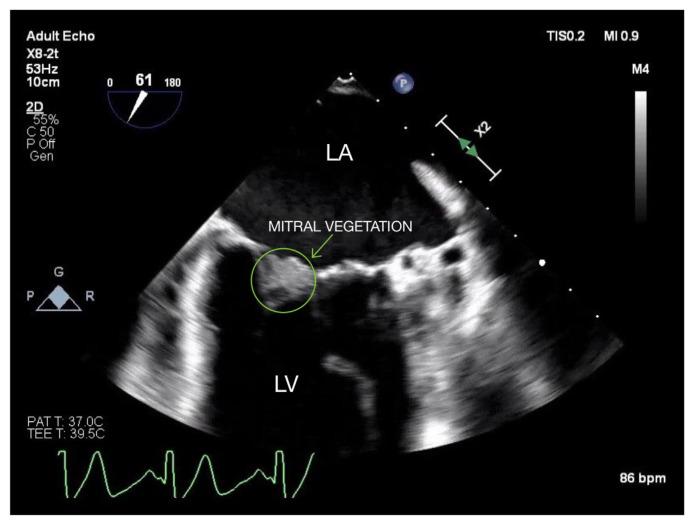

应对血栓形成和出血风险的复杂性:一名患有双瓣膜感染性心内膜炎的患者在接受心脏直视手术时出现因子 VII 缺乏和因子 V 莱顿突变的病例报告。

Managing the Complexity of Thrombotic and Bleeding Risks: Case Report of Factor VII Deficiency and Factor V Leiden Mutation in a Patient With Bi-valvular Infective Endocarditis Undergoing Open-heart Surgery.

Factor VII deficiency (FVIID) is a rare autosomal dominant disorder that occurs in approximately 1 in 500,000 individuals. Paradoxically, 3-4 percent of cases of FVIID result in thrombosis. The etiology behind this clotting predilection is thought to be multifactorial, possibly due to an associated pro-coagulant mutation. We hereby describe a case of FVIID with a heterozygous Factor V Leiden mutation (FVLM) in a patient with bivalvular infective endocarditis undergoing open-heart surgery. This case highlights the complexity of managing patients with concomitant bleeding and thrombotic tendencies, especially in the context of major surgery. We recommend tailoring anticoagulation strategies on a case by case basis to manage these risks.

摘要

因子 VII 缺乏症(FVIID)是一种罕见的常染色体显性疾病,发病率约为五十万分之一。矛盾的是,3%-4% 的 FVIID 病例会导致血栓形成。这种凝血倾向背后的病因被认为是多因素的,可能与一种相关的促凝血突变有关。我们在此描述一例患有双瓣膜感染性心内膜炎且正在接受心脏直视手术的患者,该患者存在杂合子因子 V 莱顿突变(FVLM)。此病例凸显了管理同时具有出血和血栓形成倾向患者的复杂性,尤其是在大手术背景下。我们建议根据具体情况定制抗凝策略以管理这些风险。